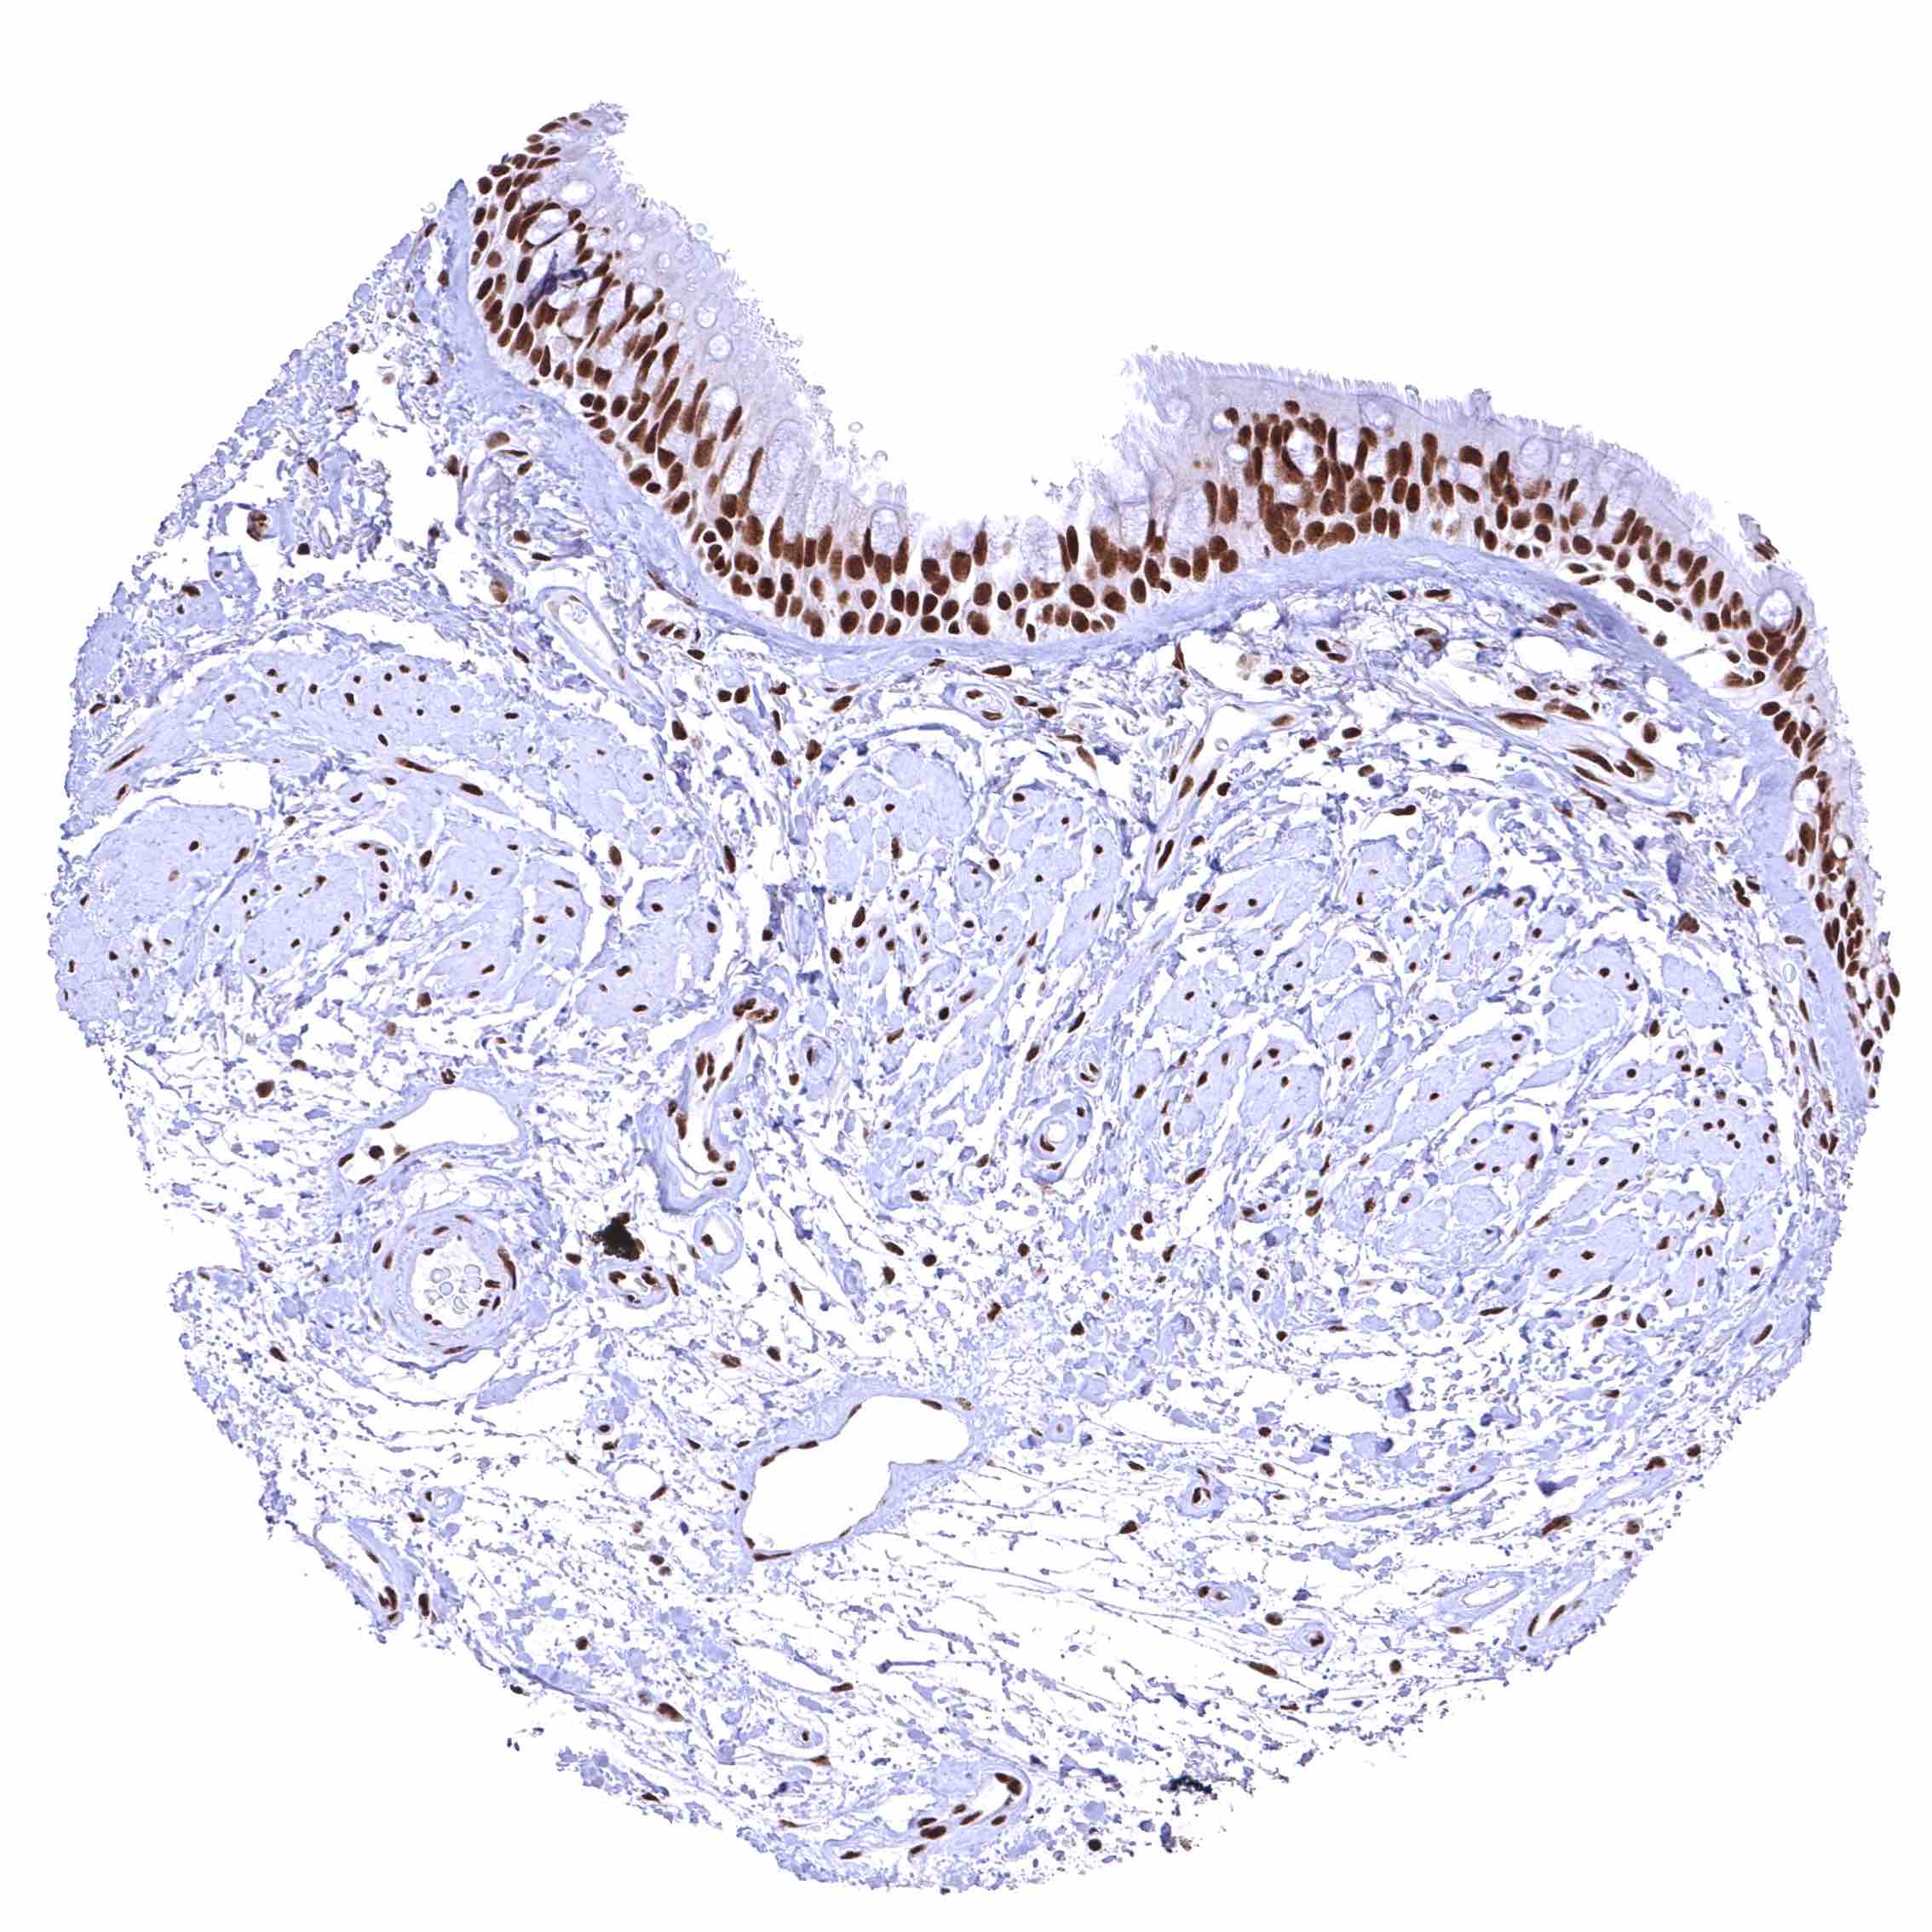

BRD4 antibody [HMV4275] HistoMAX™

Esophagus, squamous epithelium – Distinct nuclear BRD4 staining of squamous epithelial cells with a slight decrease of the staining intensity towards the most superficial cell layers.